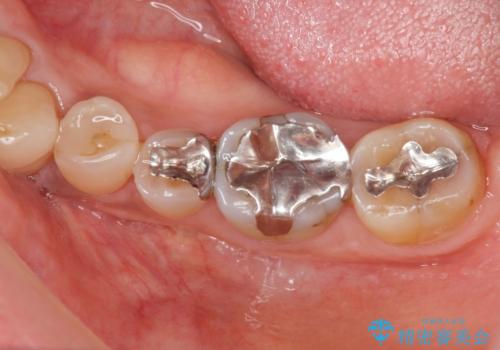

- 「老朽化し古くなった銀歯を白いものにやりかえたい。」と希望され来院されました。

銀歯の下には再発した虫歯やセメントの漏出が見られ、丁寧に除去したのちセラミックによるクラウン・ブリッジ補綴を行います。

適合や精度の悪い銀歯は、時間の経過とともに虫歯の再発リスクが高まります。